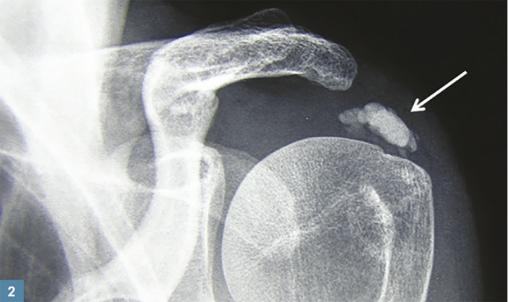

Le rhumatisme apatitique est la conséquence de dépôts de cristaux de phosphate de calcium basique, qui sont normalement présents dans l’os et la dentine. Ils sont essentiellement localisés en péri-articulaire, parfois au rachis, plus rarement dans les articulations, surtout au niveau de l’épaule (60 % des cas ; fig. 2 ), du coude et du poignet. En cas de dépôts sur plusieurs sites, on parle de « maladie des calcifications tendineuses multiples », à l’origine de douleurs chroniques polyarticulaires.

Le diagnostic est fait en général à la radiographie. Les cristaux d’apatite contiennent du phosphore et du calcium : ils apparaissent donc distinctement sur les clichés sous l’aspect de calcifications arrondies. Celles-ci se distinguent d’une ossification par l’absence de structures trabéculaires, l’homogénéité radiologique et l’apparence arrondie de leurs densités.